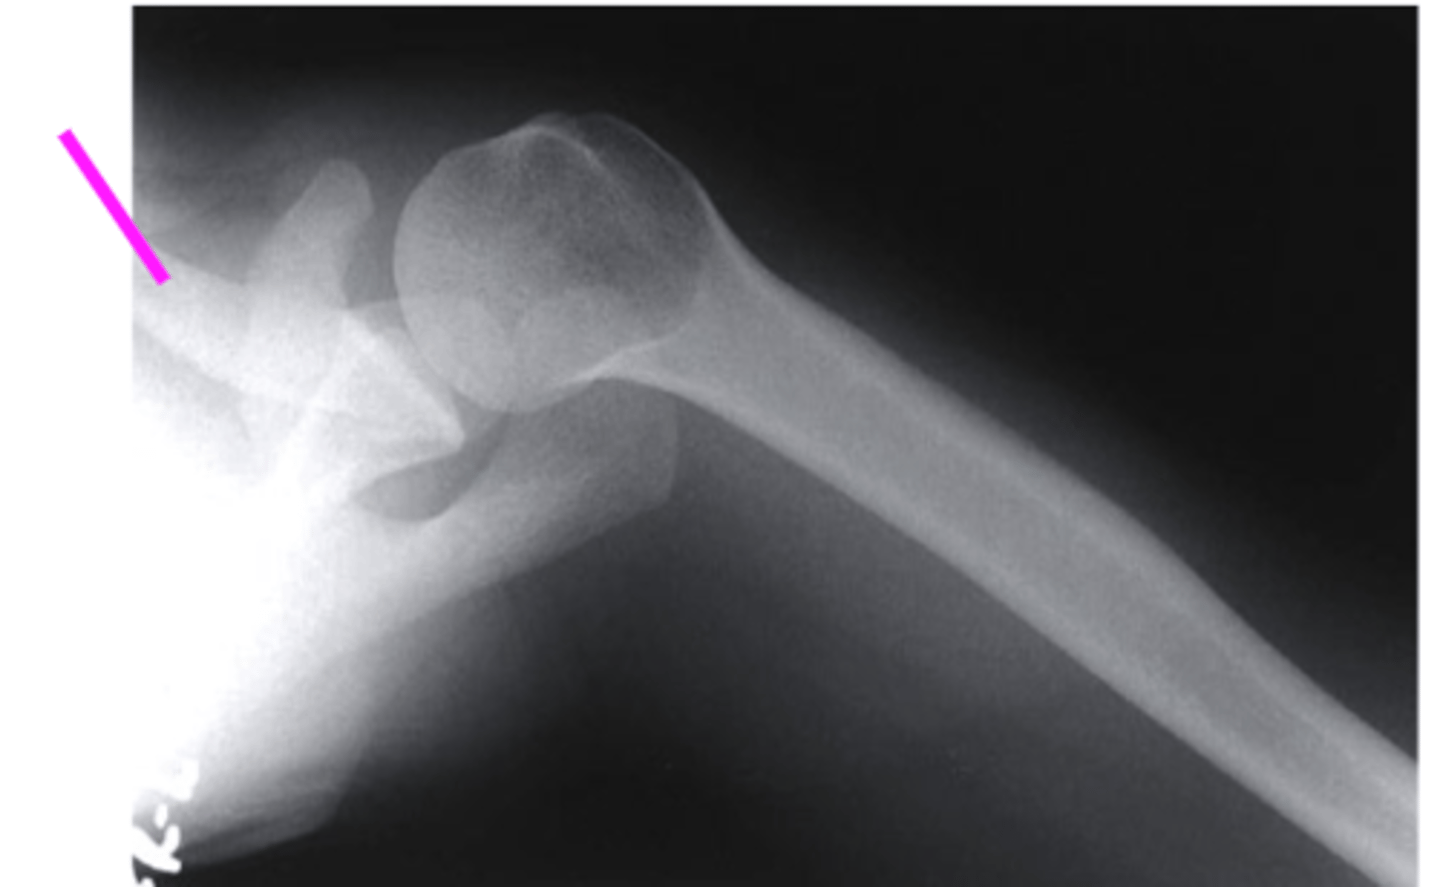

scapular Y lateral

what view is this

clavicle

what does the pink line point to?

coracoid process

acromion of scapula

humeral head

inferior angle of scapula

body of scapula